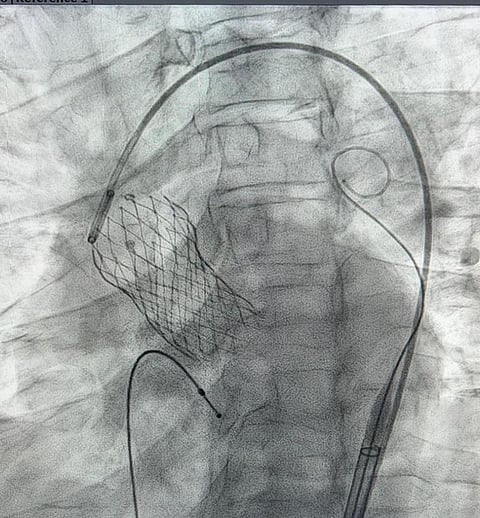

نجح طاقم طبي من الأطباء المتطوعين في جمعية "قلبي" في إجراء عملية تغيير الصمام الأورطي بالقسطرة بدلاً من الجراحة لمواطنة مسنّة تعاني بسبب ضيق وتكلس شديد في الصمام الاورطي وقصور في الكلى، والتي تكللت عملية السبعينية بالنجاح ودون أي مضاعفات ولله الحمد.

وقال لـ"سبق" المدير التنفيذي لجمعية قلبي، الدكتور حسين العنزي: قام بإجراء العملية فريق من الاستشاريين المتخصصين المتطوعين مع جمعية "قلبي" بالتعاون مع المركز التخصصي الطبي بالرياض وبتبرع سخي من شركة "ميدترونيك الطبية" التي وفرت احتياجات العملية والصمام مجانًا، مبينًا "قد يكلف مثل هذه العمليات أكثر من مائتي ألف ريال".